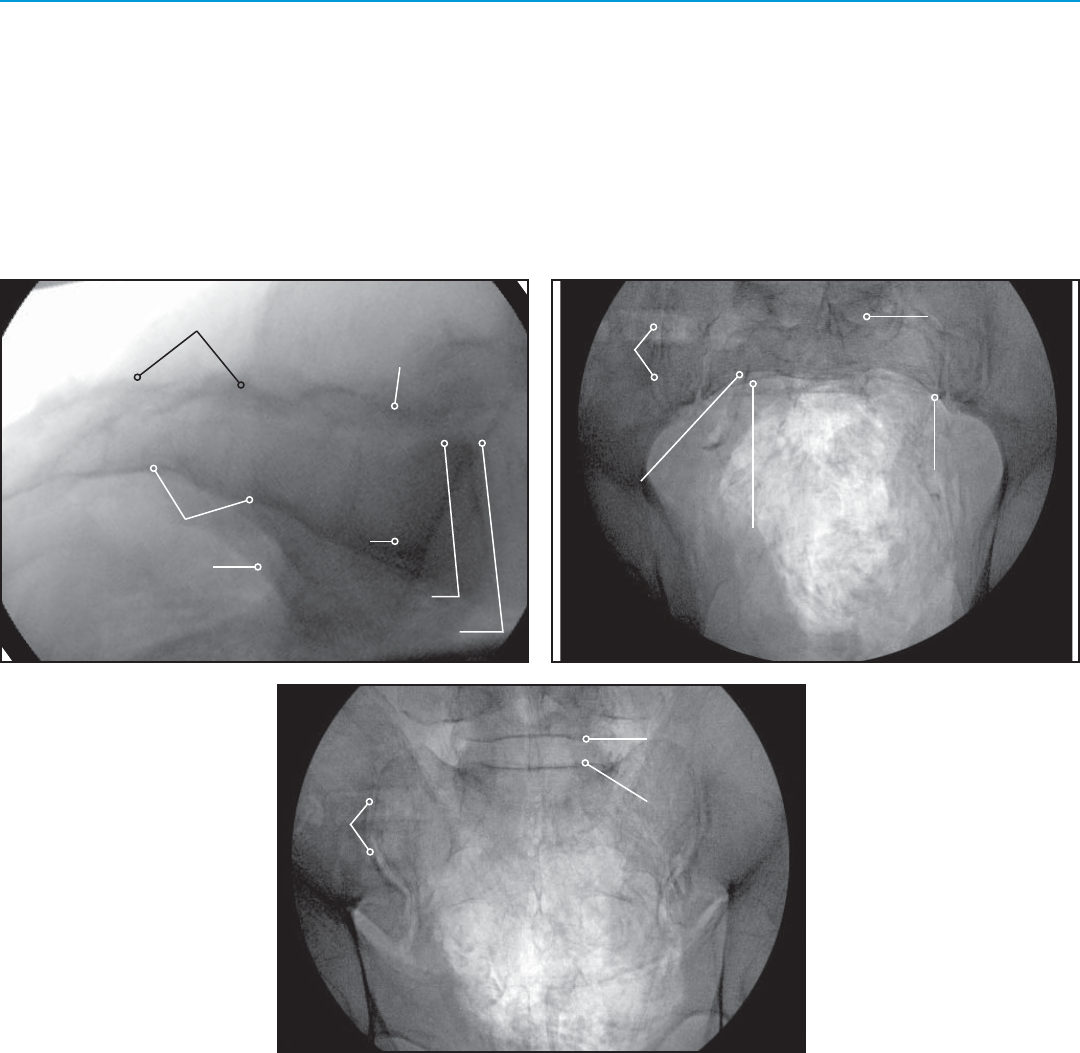

Imaging Techniques

Posterior Sacral Wall (PSW)

Ala (2 lines superimposed)

Anterior Sacral Wall

Inferior Endplate L5

Superior Endplate S1

Greater Sciatic Notch

SI Joint

Superior Alar Surface

Inferior Endplate of L5

Superior Endplate of S1

S1 Foramen

S2 Foramen

1

3

2

54

6

L5 Nerve

Pelvic Brim

23

4

5

Lateral View

Inlet View (20-25 degrees Caudally)

Outlet View (40-60 degrees Cephalad)